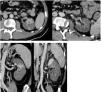

56-year-old male of Peruvian origin who was admitted from the emergency department on 31/03/2020 due to a five-day history of intense asthenia with general malaise, fever: 38.5 °C, cough and diarrhoea. He had well-controlled type 2 diabetes mellitus, a one-year history of mixed dyslipidaemia, and uncomplicated diverticulosis. He was receiving treatment with dapagliflozin/metformin and plantago ovata and adhering to a low-fat diet. On examination, he had a fever of 37.5 °C, was normotensive, and had moderate tachypnoea and sparse bibasal crackles. Height 174 cm, weight 94 kg (BMI 31). The main blood test results are summarised in Table 1. Chest X-ray with patchy bilateral interstitial alveolar infiltrates. Initiated treatment with hydroxychloroquine, azithromycin, ceftriaxone, enoxaparin 0.5 mg/kg/day and ventilatory support with nasal cannula at 2 bpm. At 24 h, the positive result for SARS-CoV-2 was received following a RT-PCR test on a nasopharyngeal swab. The patient's clinical course was unfavourable, with a greater oxygen requirement, continuous fever and an increase in acute phase reactants, so on the third day IV methylprednisolone boluses were started at 250 mg/day for 3 days, and 40 mg/day thereafter, and on the fourth day a single IV dose of tocilizumab 600 mg was administered. The patient’s condition continued to deteriorate, with clinical, laboratory and radiological progression (Fig. 1). On the sixth day, the enoxaparin dose was increased to 0.8 mg/kg/day. The patient remained stable until the ninth day, when his condition further deteriorated. The tenth day began with intense, continuous, non-radiating pain in the left iliac fossa, without accompanying bladder dysfunction. Intestinal perforation was suspected in relation to anti-interleukin treatment and an abdominal CT scan with intravenous contrast was performed (Fig. 2). Acute diverticulitis was identified and in the left kidney, hypodense, wedge-shaped areas were observed, findings consistent with extensive renal infarction, as well as associated thrombosis of the left renal artery (arrow). Renal function only showed a slight deterioration (sCr: 0.9–1.1 mg/dl and estimated GFR CKD-EPI from greater than 90–67 ml/min/1.73 m2) and the patient, who six months earlier had urine without proteinuria or haematuria and negative microalbuminuria, developed stage A3 microalbuminuria, microhaematuria and subnephrotic proteinuria. He was admitted to the intensive care unit, where he remains at the time of writing. Invasive mechanical ventilation, treatment with norepinephrine and anticoagulation with low molecular weight heparin were required. Spontaneous diuresis greater than 0.5 ml/kg/h and anticoagulation with enoxaparin. The patient’s respiratory status is improving slowly.